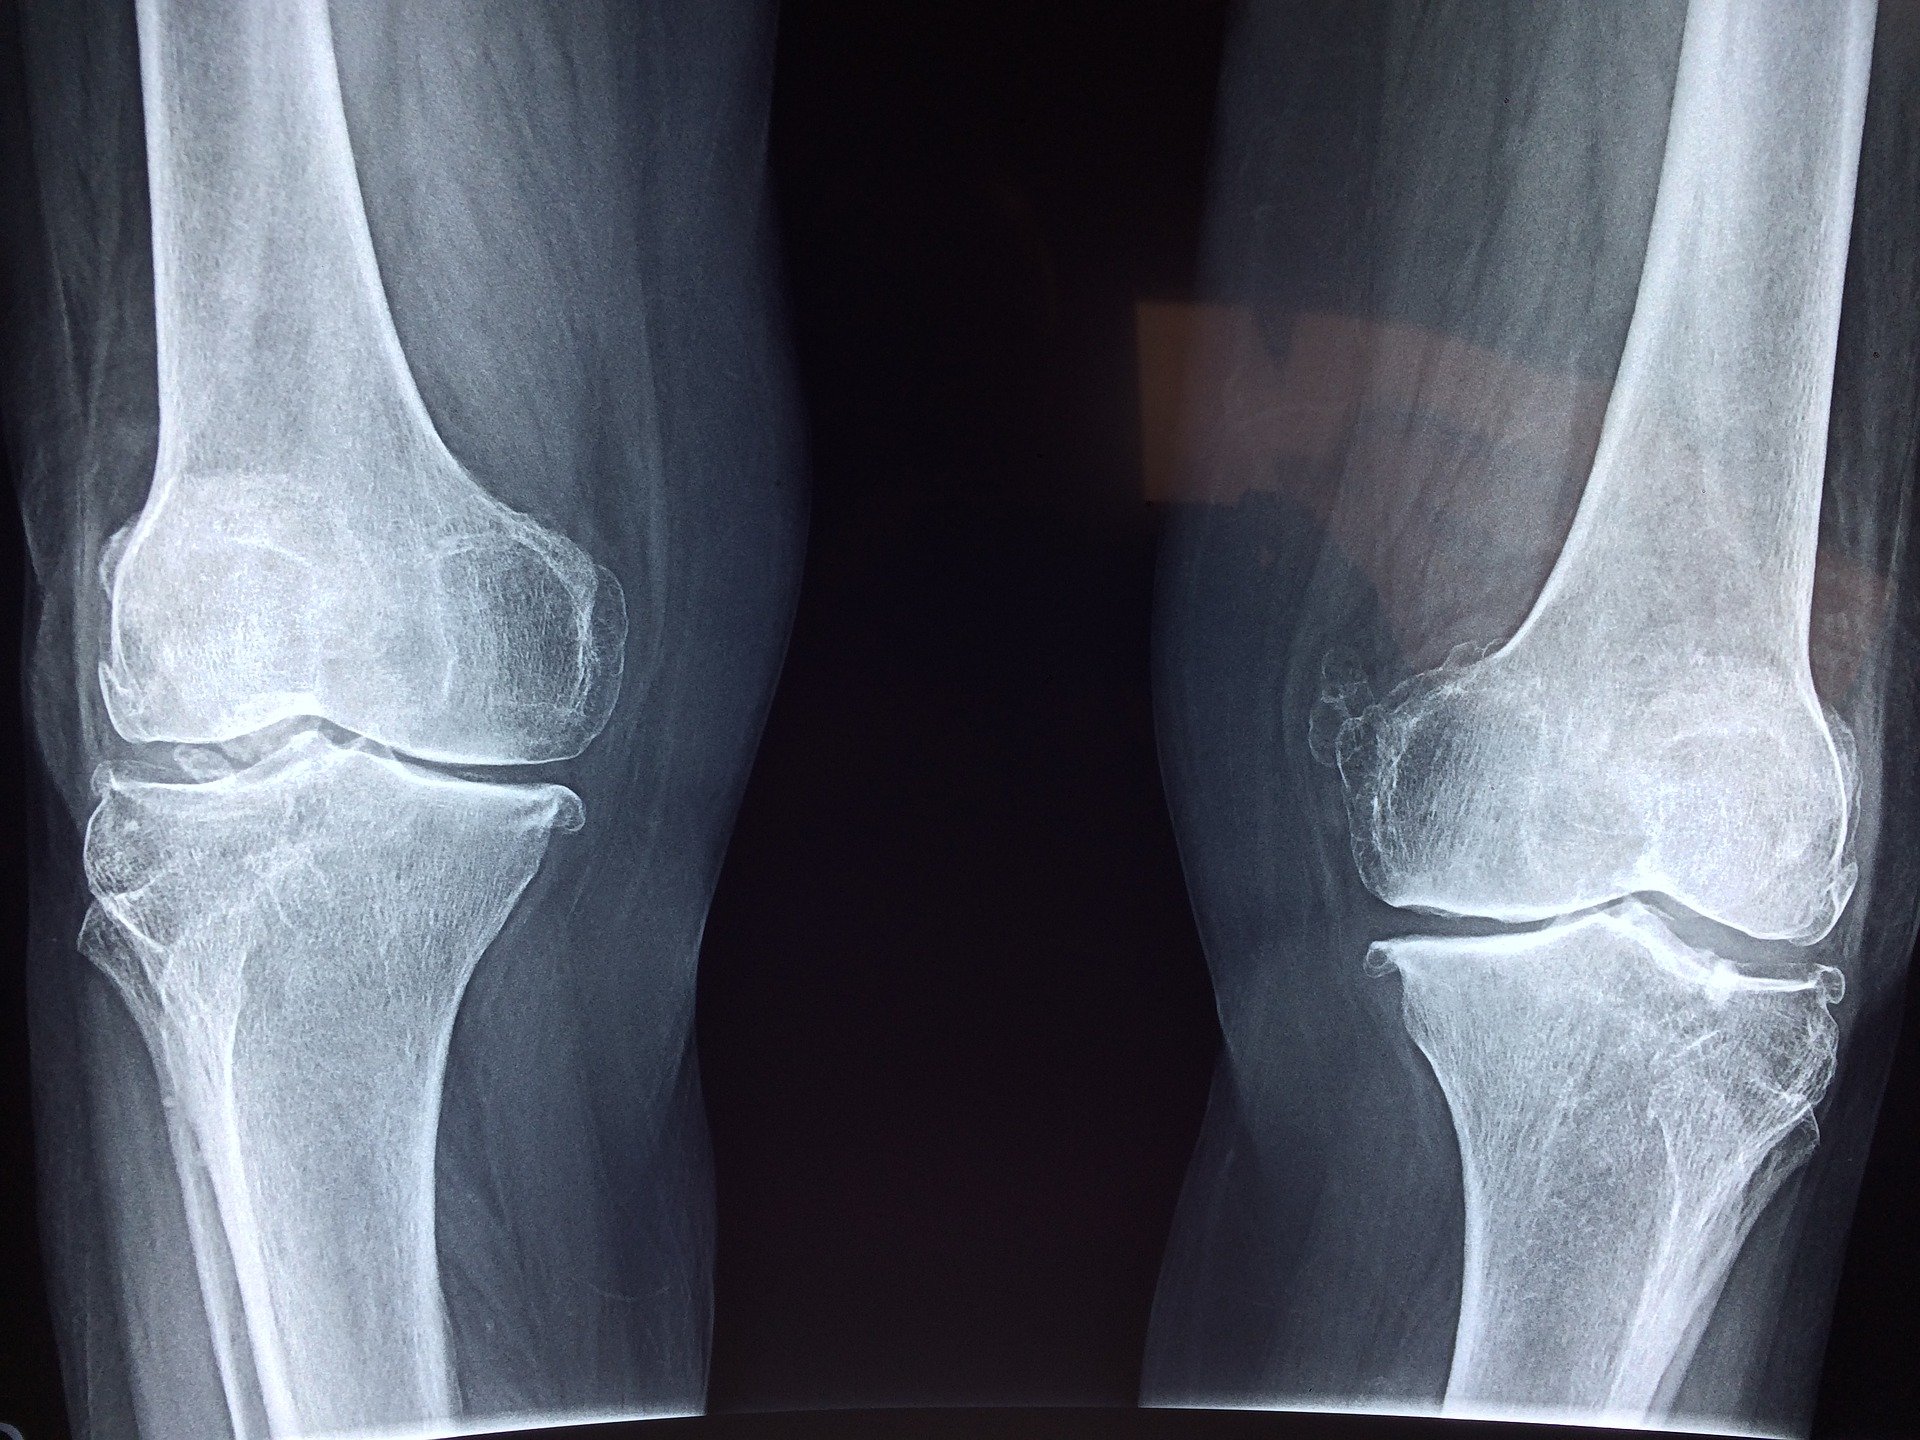

Oczywiście bolące i spuchnięte kolano, może oznaczać wiele najróżniejszych problemów zdrowotnych, zatem zawsze w pierwszej kolejności powinien obejrzeć je lekarz.